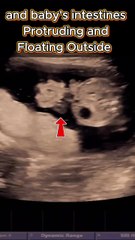

Ultrasound view of the abdominal wall